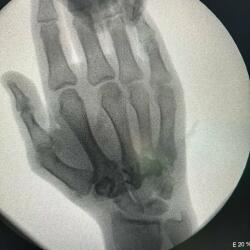

Tanınmış idmançı eyni gündə 2 dəfə əməliyyat olub. O, burnundakı çəpər əyriliyinə və sol əlindəki 3 qırıq sümüyə görə əməliyyat edilib.